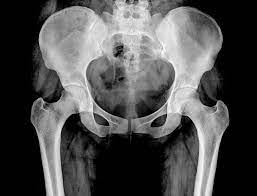

What Are The Symptoms Of Pelvic Bone Cancer : Surgical Management Of Pelvic Primary Bone Tumors Involving The Sacroiliac Joint Sciencedirect - Bone cancer destroys normal bone tissue.. More rarely, the base of the skull is affected. Chondrosarcoma is a cancer that can begin in the bones or tissue near bones, often in the hip, pelvis, and shoulder. Symptoms if cancer has spread to the lymph nodes lymph nodes are part of a system of tubes and glands in the body that filters body fluids and fights infection. The most common locations for chondrosarcoma tumors are in the pelvis, hip and shoulder. Rarely, people with a bone sarcoma may have symptoms such as fever, generally feeling unwell, weight loss, and anemia, which is a low level of red blood cells.

A high temperature (fever) of 38c (100.4f) or above It can spread to distant organs, such as the lungs. Bone cancer is rare, making up less than 1 percent of all cancers. Pelvic bone neoplasms are seldom immediately diagnosed and, therefore, may result in significant morbidity and mortality. Osteosarcoma is probably the most common disease that is related to pelvic bone cancer, with chondrosarcoma following close behind it. Hip pain is a common complaint like that of knee or back pain. At first, the pain is not constant. Bone metastases can weaken your bones and lead to symptoms like bone pain. The bones are the most common place where metastatic breast cancer cells tend to go. Chondrosarcoma is a cancer that can begin in the bones or tissue near bones, often in the hip, pelvis, and shoulder. Symptoms of testicular cancer may include: Can bone cancer be found early? Having too much calcium in your blood , which has numerous causes, is a dangerous condition called.

Bone cancer can begin in any bone in the body, but it most commonly affects the pelvis or the long bones in the arms and legs. There are many pelvic cancer symptoms a person can experience. Bone cancer develops in the skeletal system and destroys tissue. The symptoms of bone cancer are: In contrast, some other metastatic tumors, such as those from the prostate, are commonly osteoblastic, meaning that they form new bone and increase the brittleness of the bones. Rarely, people with a bone sarcoma may have symptoms such as fever, generally feeling unwell, weight loss, and anemia, which is a low level of red blood cells. Although breast cancer can spread to any bone, the most common sites are the ribs, spine, pelvis, and long bones in the arms and legs. Osteosarcoma is probably the most common disease that is related to pelvic bone cancer, with chondrosarcoma following close behind it. A primary bone cancer is one that starts from bone. Although less often, other areas (such as the ribs) may be affected. Can bone cancer be found early? Hip pain is a common complaint like that of knee or back pain. Get the latest health information from mayo clinic delivered to your inbox.